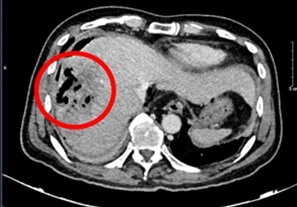

| Hình ảnh chụp cắt lớp vi tính ổ bụng của bệnh nhân. Ảnh: BVCC. |

Đáng chú ý, chỉ số AFP giảm mạnh theo thời gian, từ 648,1 ng/ml vào thời điểm bắt đầu điều trị xuống còn 9,2 ng/ml sau 20 chu kỳ, tiệm cận ngưỡng bình thường. Các kết quả chụp cắt lớp vi tính cũng ghi nhận khối u gan thu nhỏ rõ rệt, không còn tăng sinh mạch hay huyết khối. Kích thước u giảm từ 81 x 51 mm xuống còn khoảng 22 x 45 mm. Theo tiêu chuẩn RECIST 1.1, bệnh nhân đạt đáp ứng một phần.